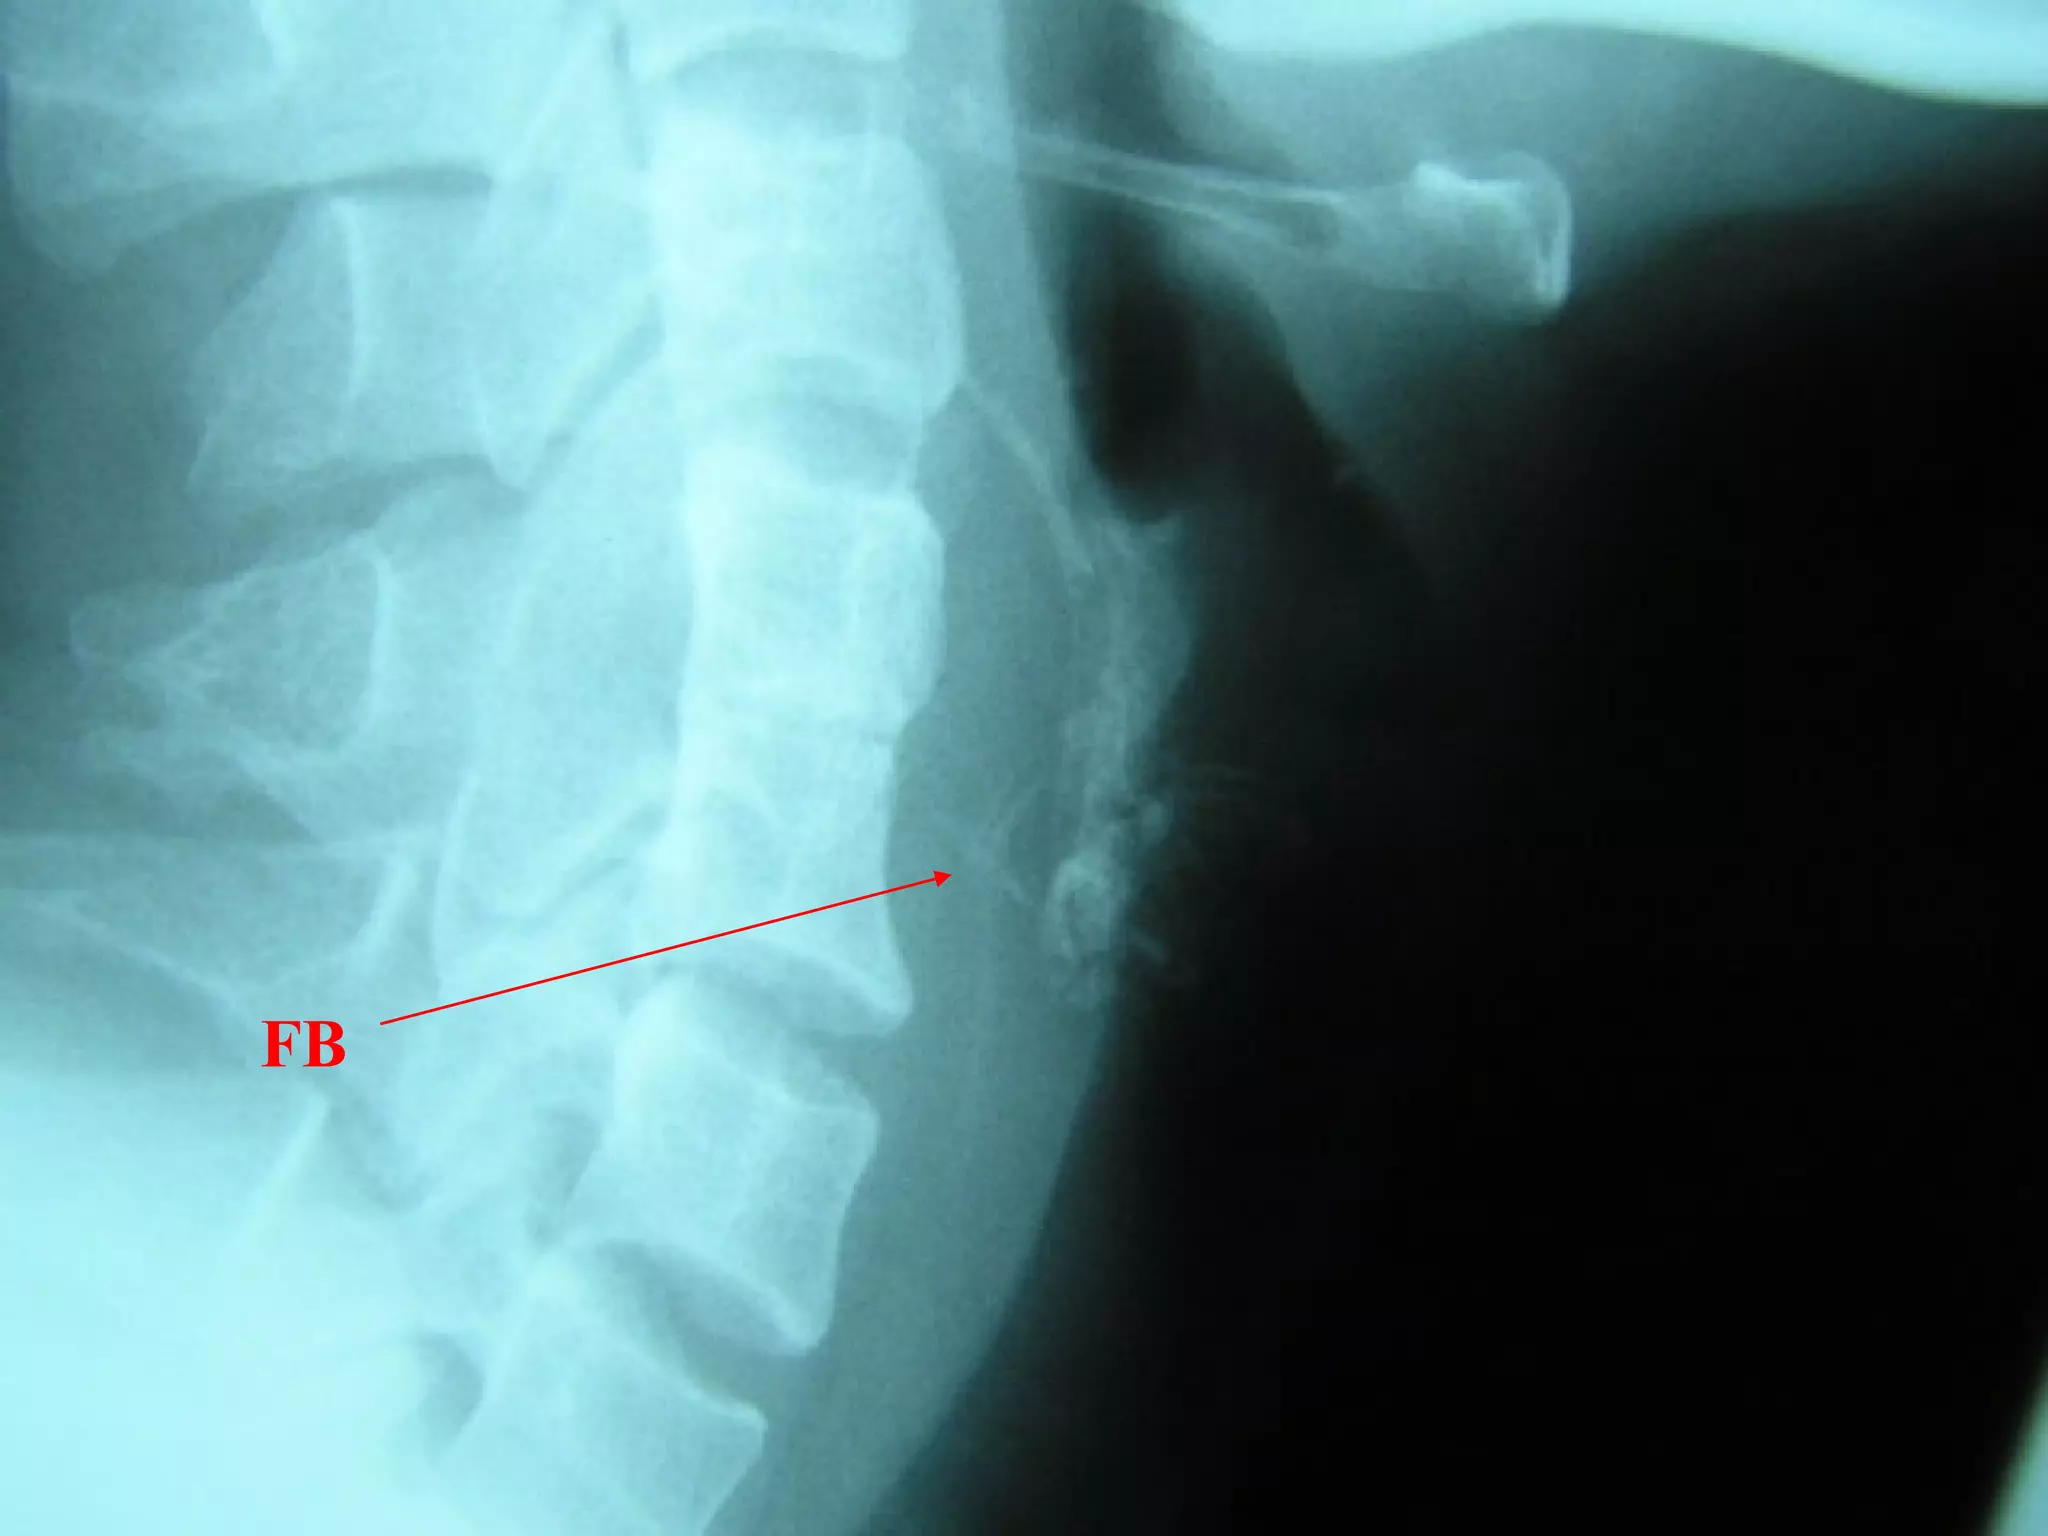

FB Throat - Investigations

Lateral neck XR

CXR

Barium swallow

CT scan – without contrast

Rigid oesophagoscopy

FB